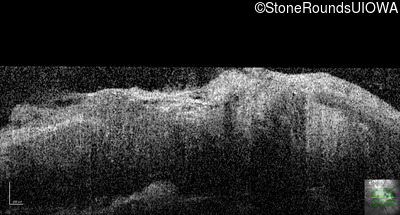

This 9 year old male was noted to have some crossing of his eyes at 2 months of age and the eye exam which followed identified a retinal lesion in the right eye. When he was six years old an epiretinal membrane was noted in his left eye. Two years later it was decided that it was a thin hamartoma in that eye as well. He underwent neuroimaging at age 7 which identified bilateral acoustic neuromas.

| Age at visit: 10 years |

| Age at visit: 11 years |

| Age at visit: 14 years |